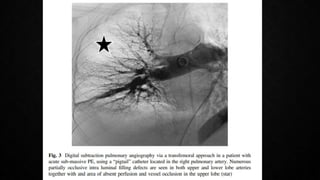

• PULMONARY ANGIOGRAPHY: Was the gold standard for decades

previously, but rarely performed now with the advent of CTPA with similar

diagnostic accuracy

OTHER DIAGNOSTIC MODALITIES •SPECT (single photon emission CT ) : V/Q SPECT or preferably hybrid SPECT/CT allows a more accurate exploration of all lung segments and better identification of segmental and subsegmental perfusion defects typical of PE Reduces the frequency of non-diagnostic studies Better sensitivity and specificity than planar CTPA, needs more evidence • PULMONARY ANGIOGRAPHY: Was the gold standard for decades previously, but rarely performed now with the advent of CTPA with similar diagnostic accuracy • MAGNETIC RESONANCE ANGIOGRAPHY: promising, needs more evidence